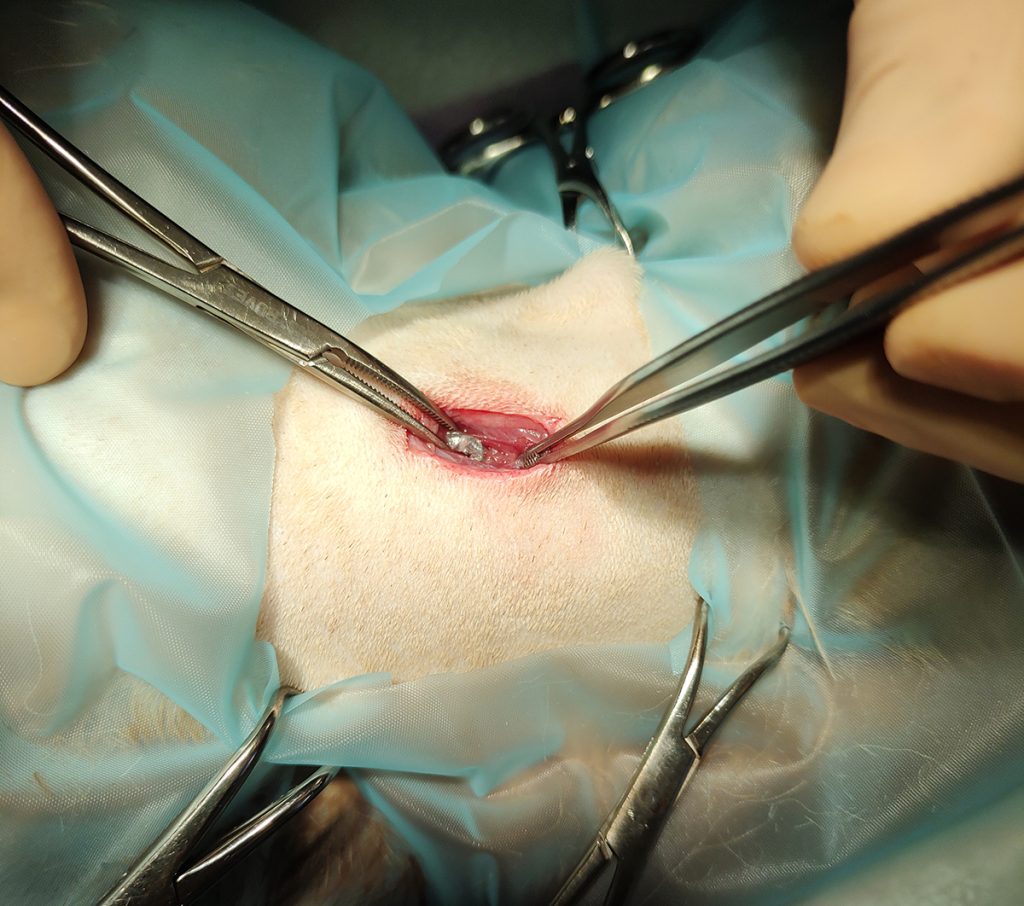

Tijdens de inspectie onder sedatie blijken zowel het harde als zachte gehemelte flink beschadigd te zijn en er is een grote scheur op de tong zichtbaar. Nu we weten waar we moeten zoeken, is ook het kogeltje in de nek voelbaar onder de huid en de spieren. Er wordt besloten Olaf dieper onder narcose te brengen om de kogelfragmentjes zoveel mogelijk te verwijderen en de wonden te hechten.

Tijdens de operatie doet Olaf het erg goed. Zijn hartslag en ademhaling blijven netjes stabiel. Bij exploratie van de wond in het gehemelte, blijkt dit een scheur tot in het bot te zijn, van ongeveer 3 cm. We kunnen zo de neusholte inkijken, wat het bloed uit de neus verklaart. Uit het gehemelte zijn 3 kogelfragmentjes en enkele losse botfragmentjes verwijderd waarna de wond gehecht is. De wond op de tong is een lange scheur over de lengterichting, die geen fragmentjes bevat. Achter in de bek is een klein gaatje zichtbaar in het zachte gehemelte, waarachter ook een gaatje in het slijmvlies van de keel zichtbaar is. Meest waarschijnlijk is dit het traject dat de kogel heeft afgelegd, tot in de nek. Helaas kunnen we het fragmentje dat achter in het keelslijmvlies aanwezig is niet bereiken. Op de neus is een wondje zichtbaar, waar op de röntgenfoto ook een fragmentje in aanwezig is. Gelukkig kunnen we deze gemakkelijk verwijderen en de huid sluiten met knoophechtinkjes. Als laatste is het kogeltje uit de nek verwijderd. Deze lag ingebed tussen de spierlagen, maar had geen grote schade aangericht op deze plek.